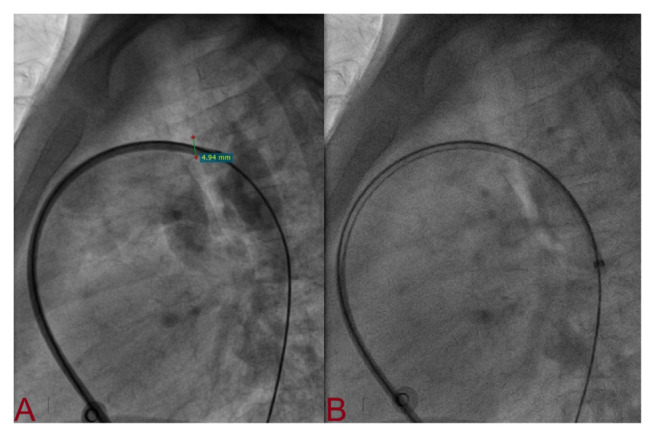

Method: In this prospective, non-randomized study, all consecutive patients with PDA undergoing transcatheter closure at LPS Institute of Cardiology, Kanpur, India between January 2019 and June 2024 were evaluated. TCC was performed using anatomical and haemodynamicl landmark without aortogram, and device was deployed through antegrade route only. Transthoracic echocardiography with colour-Doppler imaging was used to confirm position of the device before final deployment. Primary outcome was procedural and fluoroscopy time, and major complications (access site complications, device embolization, residual shunt ≥ grade 3, haemolysis, flow acceleration in left pulmonary artery and descending thoracic aorta, and death). Success was defined as complete closure of shunt without any major complications.

Result: TCC was successfully performed through antegrade route in 250 patients (age: 2.3 ± 1.2 years; weight: 10.3 ± 9.8 kg) while 16 patients were excluded for various reasons. Mean diameter of duct was 6.7 ± 4.5 mm. Male and female comprised 176 (70.4%) and 74 (29.6%) respectively. PDA were type A (n = 195; 78%), B (n = 27; 10.8%), C (n = 20; 8%), and (n = 8; 3.2%). TCC was successful in all patients although dislodgement was noted in 1 (0.04%). Lifetech duct occluder and Konar MFO were most commonly used devices in 156 (62.4%) and 33 (13.2%) patients respectively. Immediate closure was achieved in 233 (93.2%) patients while remaining 17 (7.8%) with grade I or II shunt on echocardiogram had complete closure in 2 days. Device embolization was observed in 1 (0.4%) patient while flow acceleration in DTA were observed in 5 (2%) patients. Procedure was successful in 99.6% using antegrade while TCC using isolated venous route was successful in 94%.